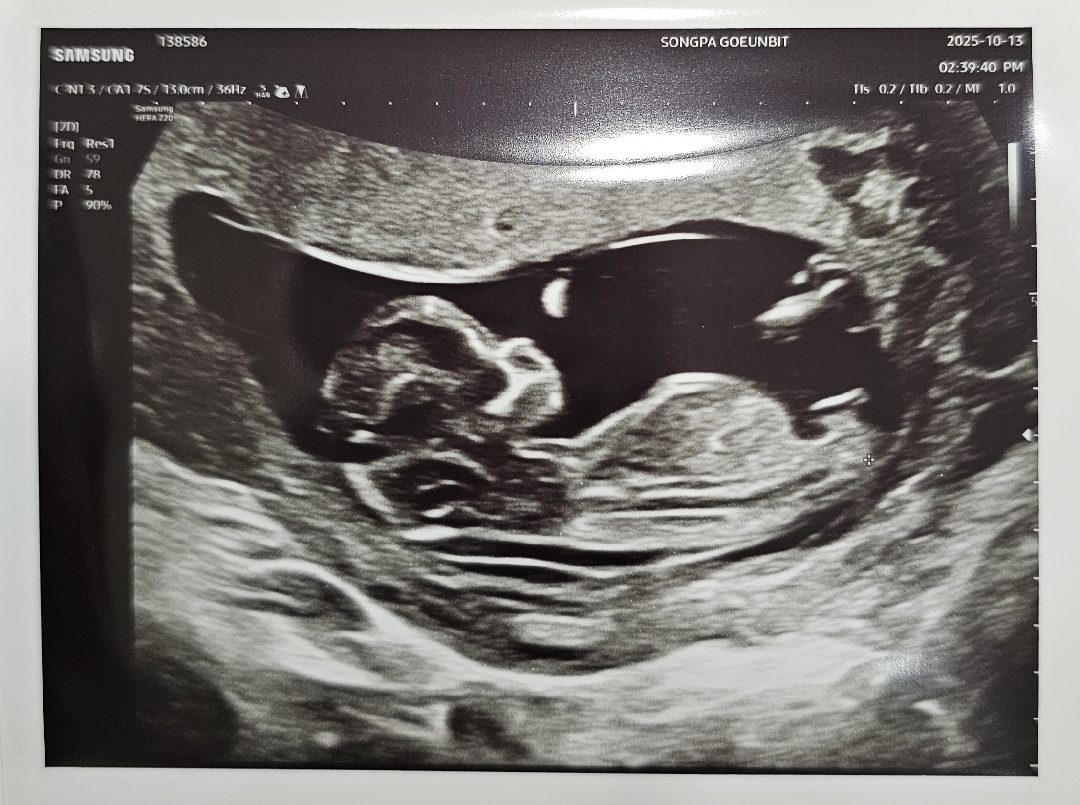

12주0일 각도법 같이 봐주실 수 있을까요

12주 0일입니다! 의사선생님께서 각도상 딸같아 보이긴 하는데 길이가 좀 긴편이라 긴가민가하다고 하시더라구요..! 근데 각도법으로는 딸같아보이긴 한다고 한번 더 말씀해주셔서 너무 궁금해요ㅠㅠㅋㅋㅋ 같이 봐주실 수 있을까요 ㅎㅎ